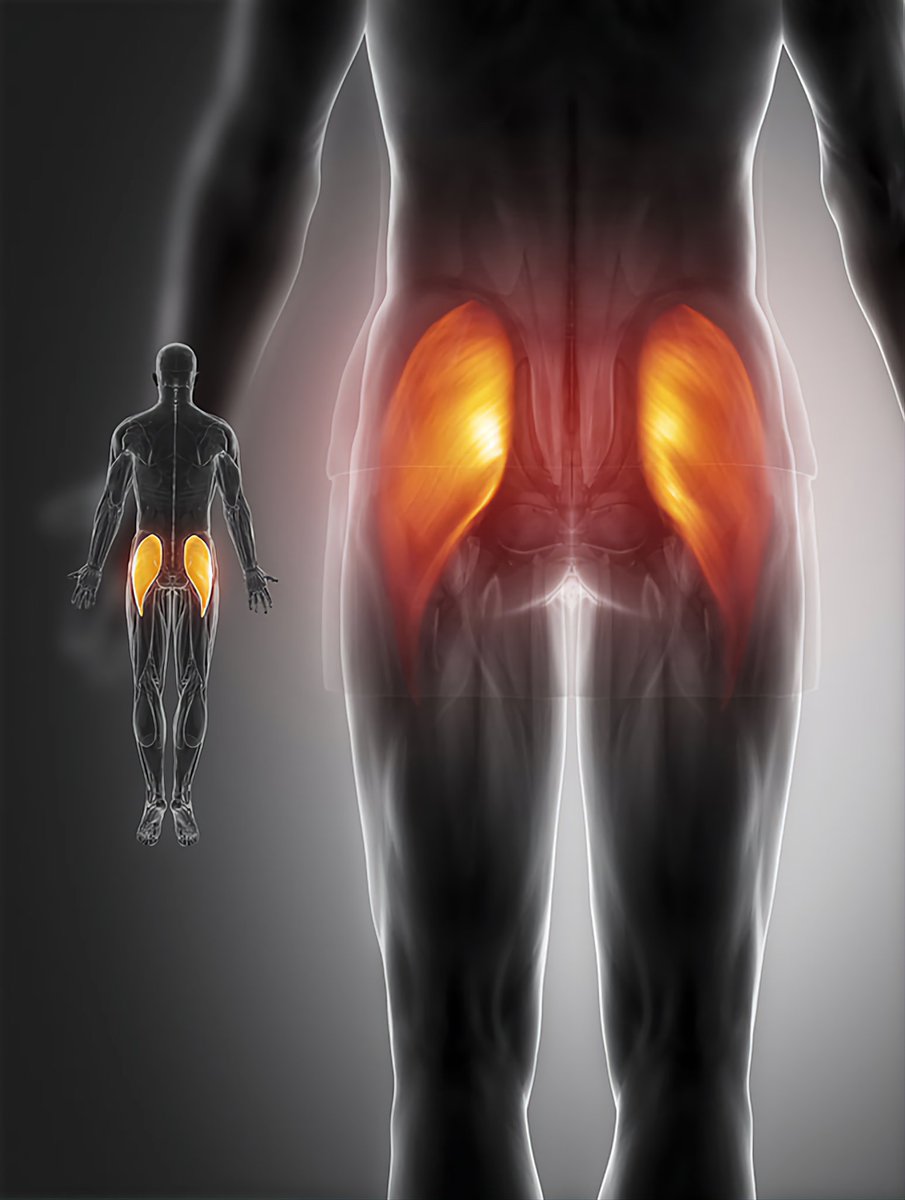

فين يكون منشأ العضلات الخلفية للرجل وخصوصا المعروفة بال Glutes وهي ( عضلات الأرداف) وأيضا عضلات ال piriformis وهي ( العضلة الكمثرية ). ⁉️

فين يكون منشأ العضلات الخلفية للرجل وخصوصا المعروفة بال Glutes وهي ( عضلات الأرداف) وأيضا عضلات ال piriformis وهي ( العضلة الكمثرية ). ⁉️